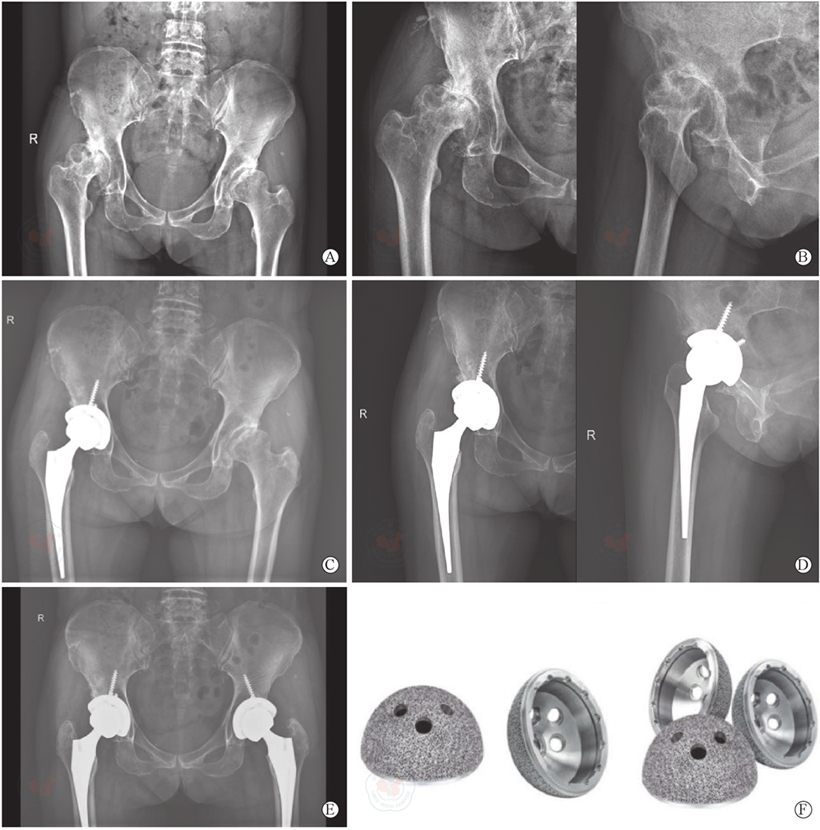

图1 标准化3D打印多孔钛合金髋臼杯关节置换术。图A为术前骨盆正位X线片,示双侧髋关节发育不良;图B为右髋正侧位X线片,示右侧Ⅱ型髋臼发育不良,合并骨关节炎;图C为术后1个月骨盆正位X线片,图D为右髋关节正侧位X线片,示右侧全髋置换术后,旋转中心复位良好;图G为术后6个月骨盆正位X线片,示双侧全髋置换后人工假体稳定,骨长入良好;图H为3D打印多孔钛合金髋臼杯

Figure 1 Images of the patient undergoing standardized 3D printed porous titanium alloy acetabular cup arthroplasty. A is the anteroposterior X-ray image of the pelvis before operation, showing bilateral developmental dysplasia of the hip; B is the anteroposterior and lateral X-ray image of the right hip, showing typeⅡ acetabular dysplasia of the right hip, combined with osteoarthritis; C is the anteroposterior X-ray image of the pelvis at one month after surgery, D is the anteroposterior and lateral X-ray image of the right hip, showing the right hip with good reduction of the rotational center after total hip arthroplasty; G is the anteroposterior X-ray image of the pelvis at six months after surgery, showing stable prostheses in bilateral total hip arthroplasty and good bone ingrowth; H is the 3D-printed porous titanium alloy acetabular cup